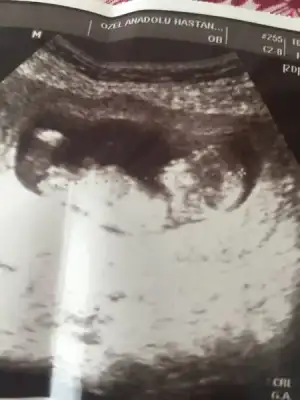

Sağol canım Allah razı olsun. Hiçbirşeyden tiksinmedim, koku hassasiyetim oldu ama kokular güzel geldi rahatsız etmedi, iki gebeliğimde de hiç bulantım olmadı, ikisinde de kanama oldu, bunun dışında çok rahat gebelik geçirdim, sadece tatlı şeyler istiyorum ve tüketiyorum, bir öncekiyle ultrason görüntüleri keselerini falan karşılaştırıyorum çok benzer.

canım benim bebeğime de bakar mısın?

Eklentiler

• 78F8C7B8-26D2-499A-9EF8-9BF6D0AB06CD.webp

78F8C7B8-26D2-499A-9EF8-9BF6D0AB06CD.webp

12,9 KB · Görüntüleme: 83